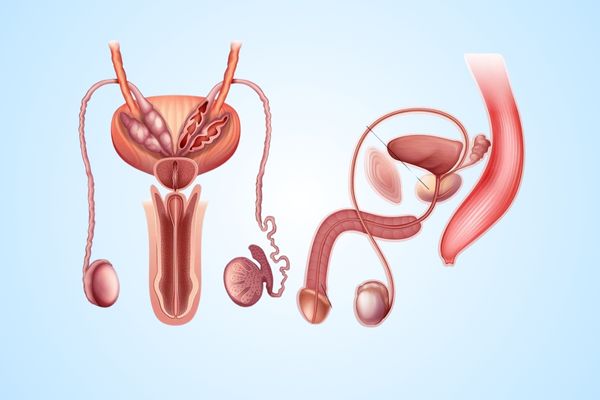

Sourav k

After months of frustration, I consulted Dr. Omang for infertility issues. His treatment plan worked, and today, my wife and I are expecting. He gave us hope when we had none.